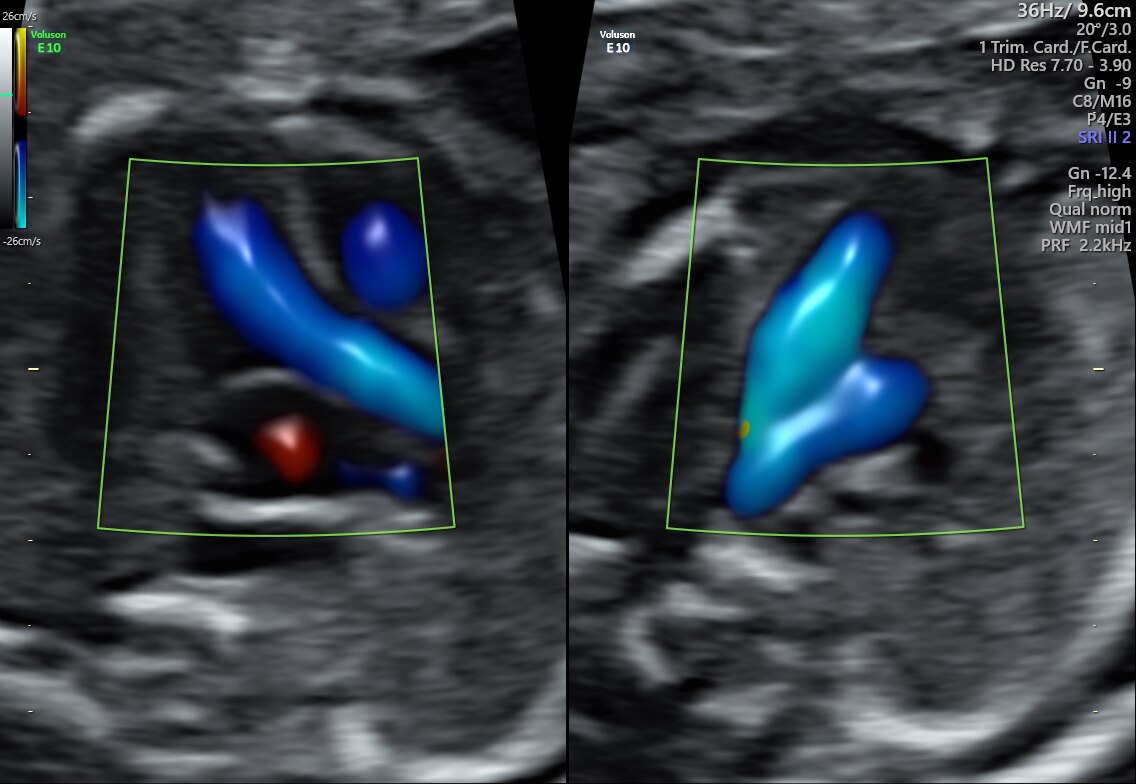

15-week fetal circulatory system with eSTIC and HD-Flow™

3VV and LVOT with Radiantflow™ in Dual Display